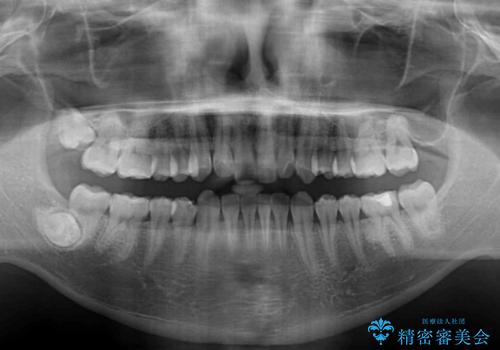

上下前歯にデコボコがありましたが、特に上顎の叢生が強く、通常に歯列を整えると、上顎が前方に突出し、口元の突出感が残った仕上がりとなる可能性が考えられました。

補助装置を用いて上顎歯列全体を後方に移動させる力をかけ、唇が閉じやすいような仕上がりを目指して、ワイヤー装置にて矯正治療を行うこととしました。

非常に咬合力が強く、左側の臼歯がなかなか後方へ移動できなかったのですが、2年ほどかけて大変満足のいく仕上がりを達成することができました。